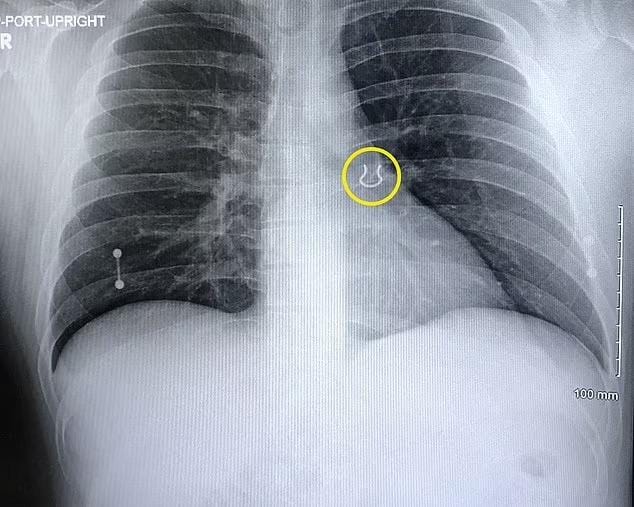

واستقر حلقة الأنف في رئة الرجل، بعد أن أخذه للأشعة السينية، بسبب مخاوف من السعال الشديد كان علامة على التهاب رئوي.

الحلق مغروس داخل الفص الأيسر

وخشي الأطباء أن تكون هذه علامات تحذيرية للالتهاب الرئوي، لكن الأشعة السينية أظهرت أن الحلق كان في الواقع 0.6 بوصة، التي كان يرتديها في الحاجز، مغروسة داخل الفص الأيسر العلوي من رئته.